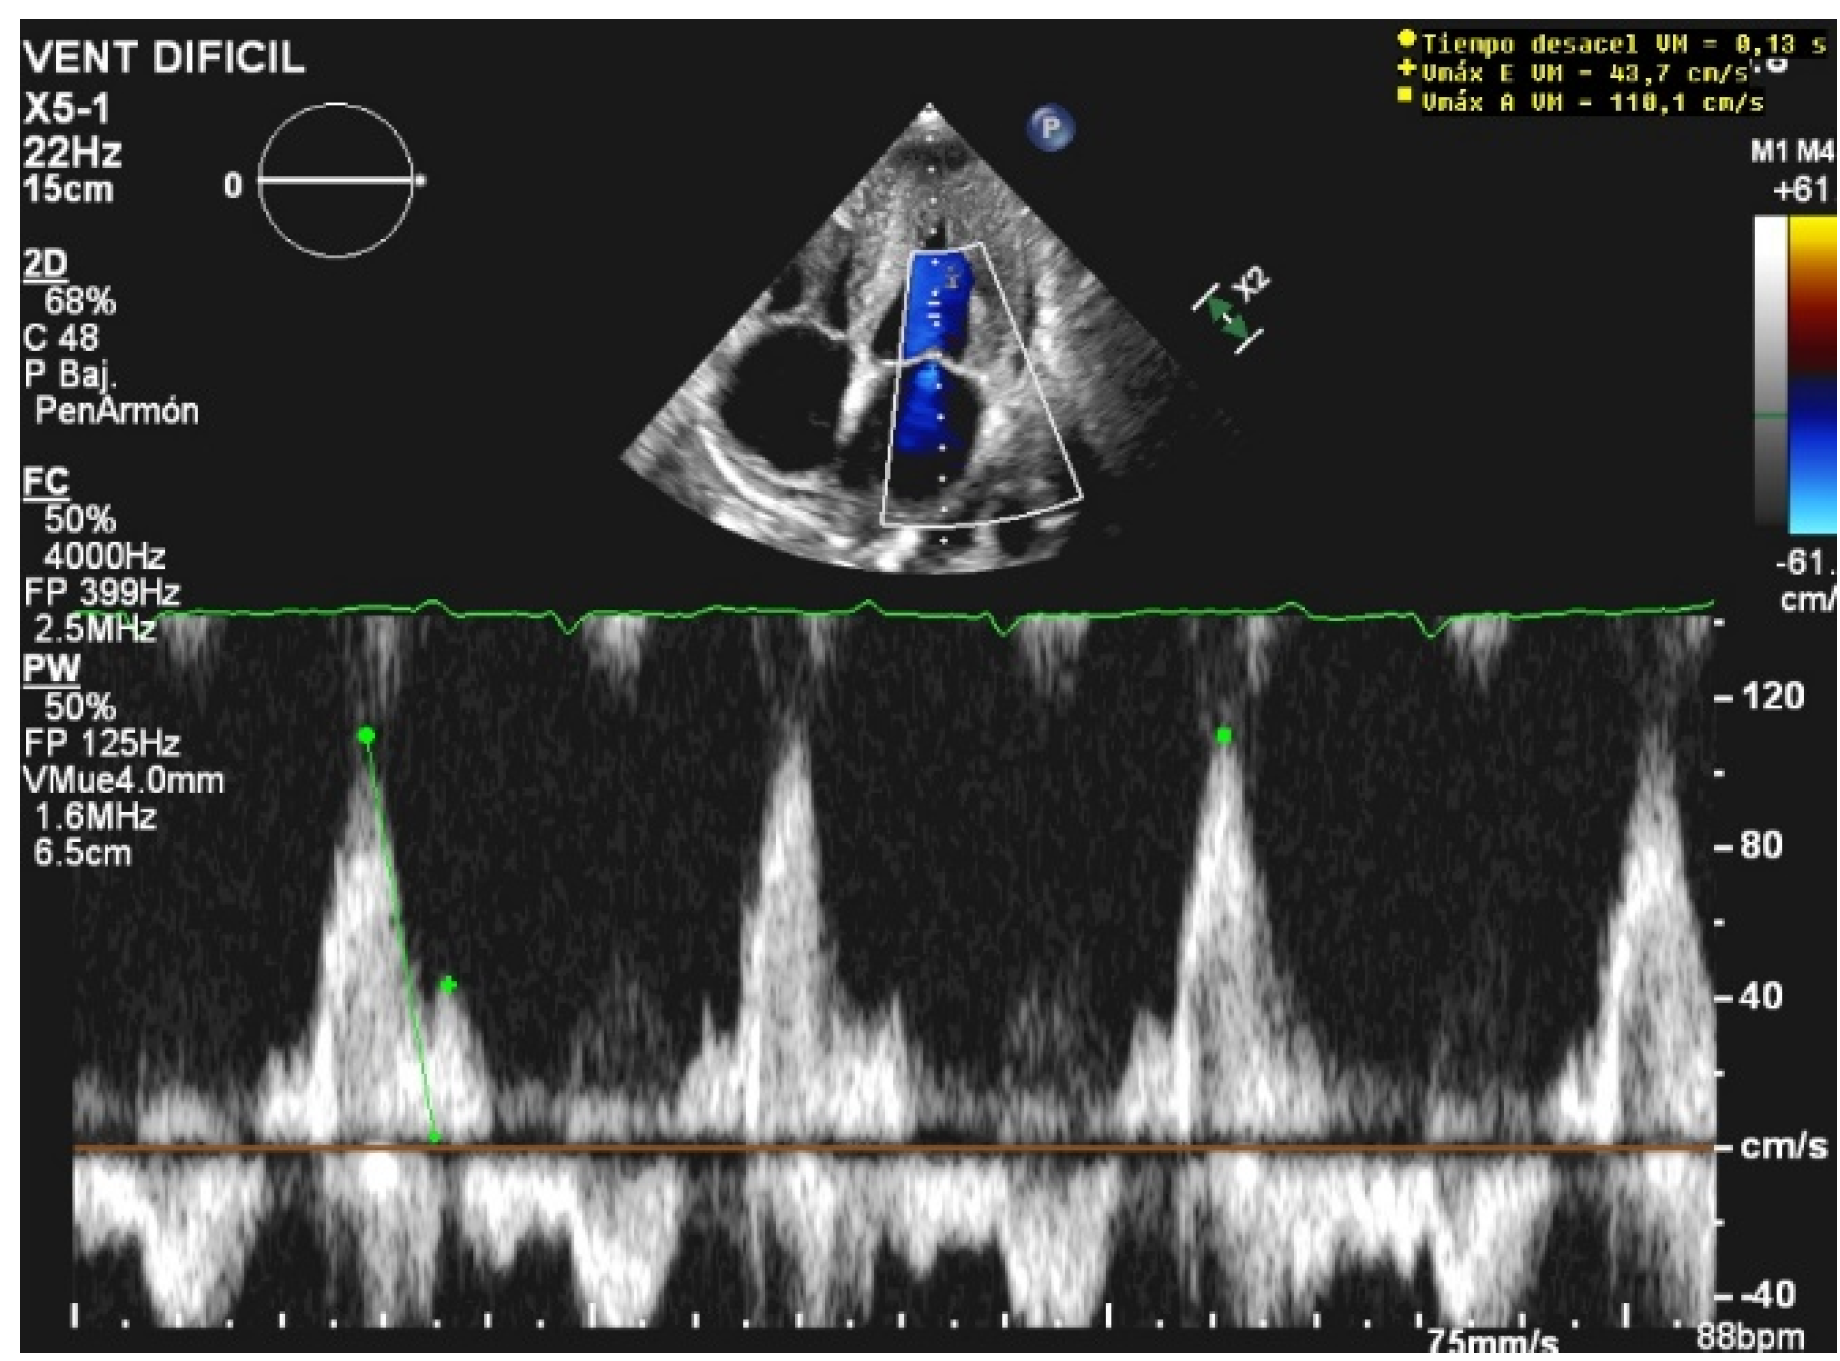

The E/A ratio is not useful in critically ill situations, as this parameter frequently suffers from a “pseudonormalization” issue [13], with a difficult quantitative interpretation. However, the presence of a “pseudonormal” or restrictive pattern is related to higher rates of weaning failure [20] (Figure 2). A reduction in the E wave deceleration time below 175 ms, in addition to other parameters which can reflect diastolic impairment, such as raised left-atrial pressure indicated by interatrial septal fixed rightward curvature and left-atrial area larger than 25 cm2, is a significant predictor of extubation failure [21]. Moreover, failure is significantly associated with a higher pulmonary capillary edge pressure and elevated pulmonary venous systolic filling [20].

Figure 2.

Restrictive diastolic filling pattern.